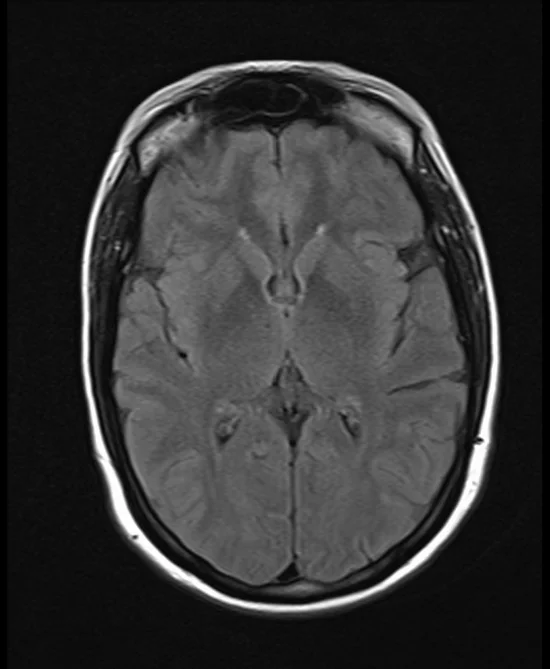

brain mri t2 flair axial images